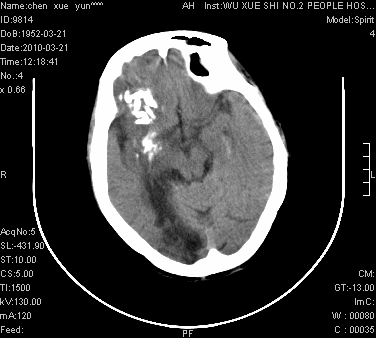

性别:不详;年龄:58岁;病史:不详。

ct表现:1、右侧额颞叶深部不规则钙化密度团块,呈弯曲条带状,占位效应不明显,考虑少枝胶质细胞瘤可能性大于血管瘤。2、右枕叶大片不规则低密度影,密度近似于脑脊液,右侧侧脑室后角及三角区扩张,考虑为陈旧性脑梗塞。

讨论:1、这个病灶的钙化有点像脑回样钙化,因此我最初考虑颅面血管瘤病(sturge-weber综合征),但是查阅了我们网站上的几个颅面血管瘤病病例,钙化均位于脑实质表面,沿脑回分布,而这例病灶位置较深,因此可以否定“颅面血管瘤病”这个诊断。

2、卜一会员曾经说过:少枝胶质细胞瘤的典型征象为弯曲条带状钙化,可作为定性的可靠征象(http://www.radida.com/news_view.asp?id=5150)

3、血管瘤也可以出现弯曲条带状钙化,但血管瘤多数出现“负占位”效应,即病灶周围的脑室、脑池及脑沟不是受压变窄,而是局限性的增宽。